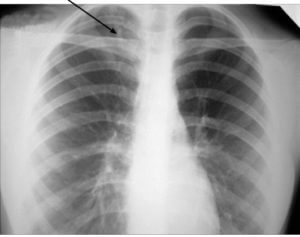

Данные флюорограммы служат основанием для постановки различных диагнозов. Большое значение имеет прохождение флюорографии у больных туберкулезом, начало которого протекает бессимптомно. Ранняя диагностика этой болезни помогает получить медицинскую помощь своевременно и минимизировать риск развития осложнений, летального исхода. Флюорография дает возможность выявить и другие заболевания:

- Воспалительные заболевания (воспаление легких – пневмония, бронхит, плеврит) и их очаги;

- Фиброз (уплотнение ткани соединительного типа);

- Обструкции в бронхах;

- Наличие инородных предметов в дыхательных путях;

- Патологические полости – абсцессы, кисты;

- Газ в полостных участках;

- Наслоение плевры ее сращение;

- Грыжа, купола диафрагмы;

- Скелетно-мышечные отклонения;

- Сердечнососудистое заболевание.

Кроме того, на флюорографии видно, если человек подвержен курению. От здорового легкого органы дыхания курильщика отличаются увеличением ширины легочных стенок, тяжистыми корнями. Так выглядят снимки людей, имеющих большой стаж. Это необязательно говорит об опасных патологиях.